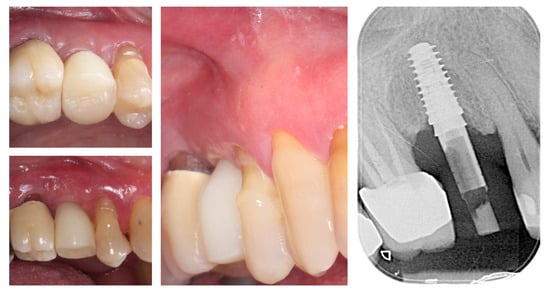

Three months postoperatively, the peri-implant site demonstrates complete mucosal healing with stable, well-contoured soft tissues. The healing abutment is visible in situ (left), with healthy, keratinized mucosa surrounding the transmucosal interface. Following removal of the healing abutment (middle), the implant platform shows a mature and stable soft tissue collar without signs of inflammation, recession, or dehiscence. The X-ray control reveals stable crestal bone levels without signs of bone remodelling (right) (Figure 12). The roll flap augmentation resulted in increased buccal tissue thickness and harmonious gingival architecture, providing favourable conditions for prosthetic restoration.

Figure 12.

Mature peri-implant mucosa and stable crestal bone after roll flap augmentation (3 months post-op).